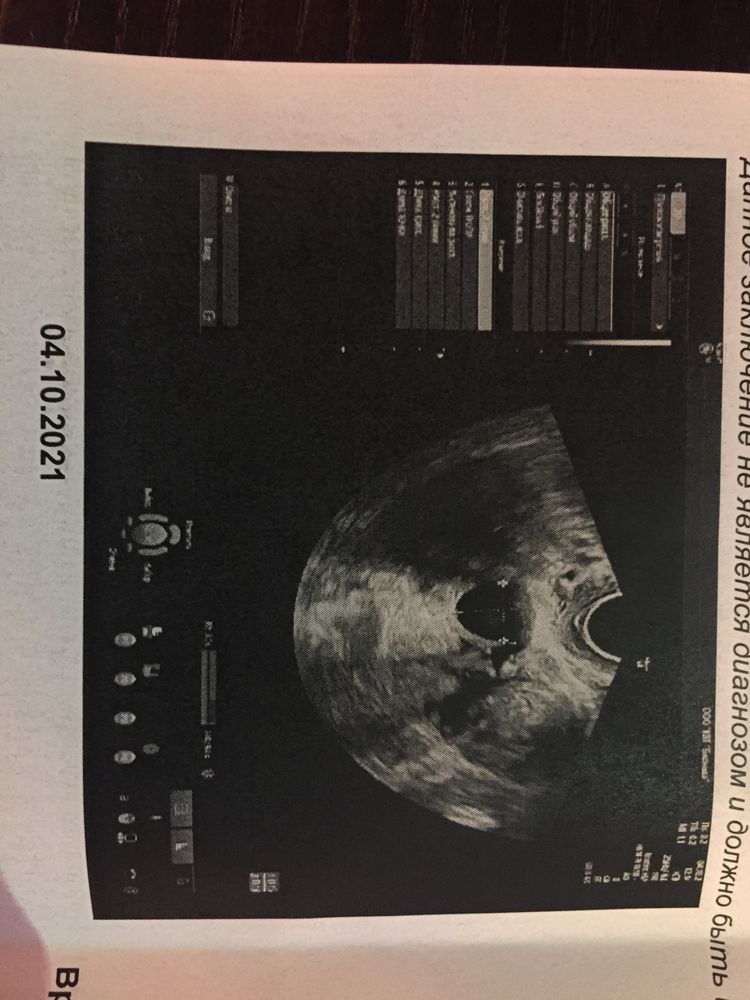

нужен совет, в течение полугода мне в разное время цикла в пя находят фолликул 16х17, он никуда не уходит после месячных. Сейчас описали как образование... как оно появилось, пропала О, и месячные свои потерялись, вызываю дюфастоном от...что это и почему не исчезает?

Это киста у вас. Вам бы на ОК месяц-два посидеть она пройдет. Если не пройдёт, то нужно будет лапара